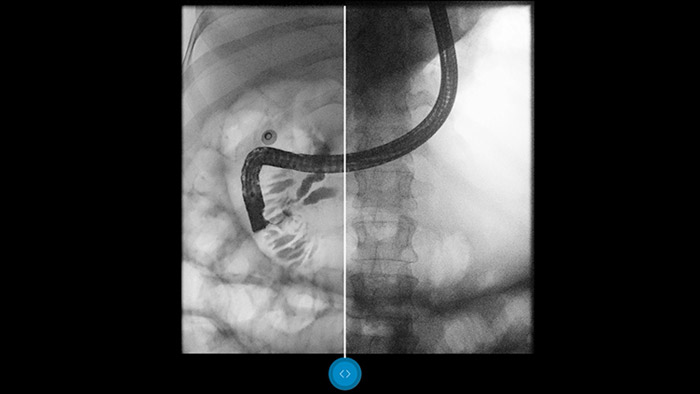

Porównaj bezpośrednio z obrazami po konwencjonalnym przetwarzaniu i zobacz korzyści dla siebie.

Dynamic UNIQUE delivers excellent detail with overall contrast harmonization – even in challenging viewing conditions. Each and every frame is fully processed in real-time and optimally enhanced. There are no enhancement artifacts. There is no image clipping. So you are less likely to miss important details*.